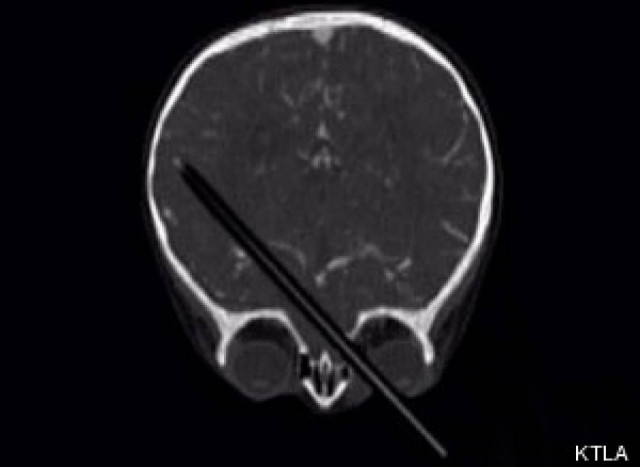

Ζούσε επί 15 χρόνια με ένα μολύβι καρφωμένο στο κεφάλι του

ΚΟΣΜΟΣ · 30.05.2013 - 17:10

Γερμανοί γιατροί ισχυρίζονται ότι ένας 24χρονος ζούσε με ένα μολύβι επί 15 ολόκληρα χρόνια μέσα στο κεφάλι του, σύμφωνα με δημοσίευμα της Huffington Post.

ΦΡΙΚΗ: Μολύβι καρφώθηκε στον εγκέφαλο ενός παιδιού 2 ετών

ΚΟΣΜΟΣ · 28.01.2013 - 10:01

Από θαύμα σώθηκε το μόλις 19 μηνών παιδάκι το οποίο έπεσε από το καρεκλάκι του και έπεσε πάνω σε ένα μολύβι το οποίο διαπέρασε το…